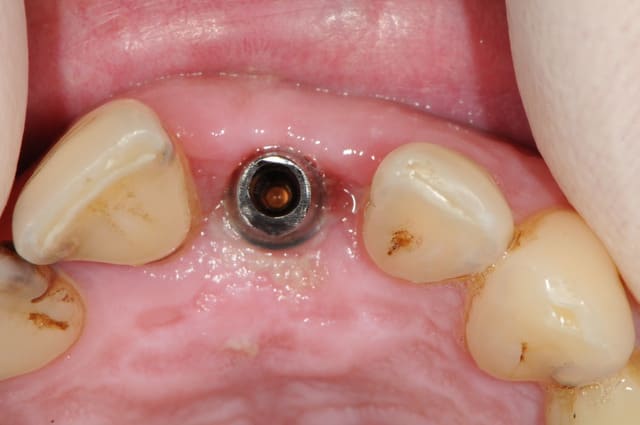

au cas où vous ne fait la provisoire immediatement, vous pouves choisir le" one stage procedure" . Dans ce cas, vous conservez la profile de la gomme avec une "gingiva former".

Avec un parodonte épais comme celui-ci, former la gencive n'est pas trop difficile.

Un pilier de cicatrisation customisé ou personnalisé c'est une vis de ciatrisation individualisée : elle peut être faite de plusieurs facons par exemple à partir de ton porte implant que tu modifies par apport successif de composite.

Ca ressemble à cela :